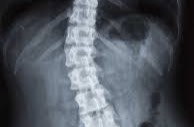

The Three Major Root Causes Of Back And Hip Pain

The Inverted Back Protocol

Everything you need to know about correcting your lower back issues and be pain free.